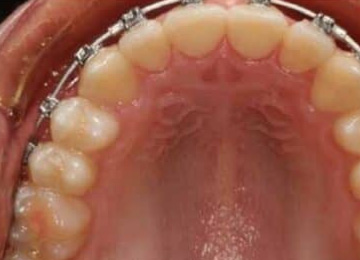

Брекеты: фото До и После

Брекеты могут размещаться как с наружной стороны зубного ряда, так и с обратной (лингвальные), по направлению к ротовой полости. Лингвальная конструкция брекетов может повлиять на произношение и усложнить процесс принятия пищи, но такой вариант установки выбирают за ее незаметность. Тонкая полоска металлического каркаса не привлекает к себе внимания. А если на слизистой щек были травмы, этот вариант становится наиболее предпочтительным.

Процедура установки брекетов и сроки ношения

Процесс установки брекетов протекает спокойно и не занимает больше полутора-двух часов. Для начала проводится профессиональная чистка зубов, после чего ротовая полость промывается и просушивается. Используются антисептические препараты, после чего наносятся составы адгезива и праймера, благодаря которым и будут фиксироваться накладки. Производится фиксация, избытки клеящего состава удаляются, после чего начинается процесс полимеризации. Для этого используется световое излучение.